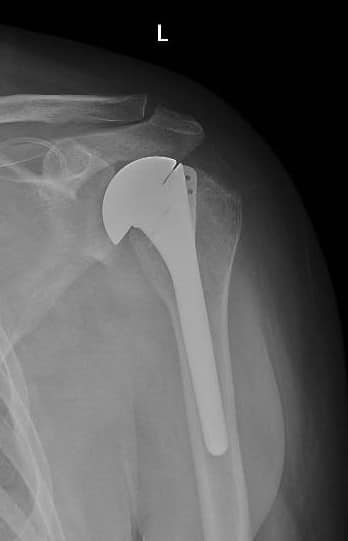

Un tânăr giurgiuvean diagnosticat cu necroză a capului humeral,în luna noiembrie 2023, a primit șansa la o viață normală, după implantarea unei proteze de umăr în cadrul serviciului de ortopedie și traumatologie.

Este de menționat faptul că acest tip de intervenție chirurgicală se face doar într-un număr limitat de unități medicale din Romania.

La doar două luni de la intervenție, tânărul este recuperat în proporție de 80%.